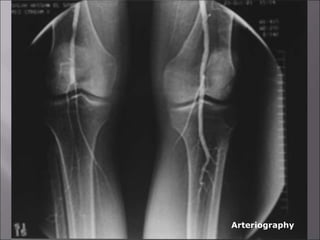

 -Angiography

- Arteriography

Arteriography

1- Laboratory investigations: 2-Imaging: - Doppler flow study. • ABI • Segmental pressure - Duplex scanning - Arteriography Arteriography